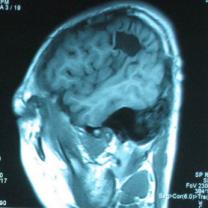

头颅CT和MRI可见颅骨缺损区下方软脑膜囊肿、脑软化灶或脑室穿通畸形(图2)。

图2:①和②CT及骨窗相显示右顶部颅骨缺损,其下方脑组织呈低密度改变;③-⑥MRI右顶局部颅骨缺如,脑组织轻度向外膨隆,右顶叶侧脑室体部旁局部脑组织缺如,代之以囊性长T1、长T2信号。

结果及随访:术后一周复查头颅CT显示脑室穿通畸形明显缩小(图6)。随访3年,未出现癫痫发作。得到很好的治疗,回归社会,正常生活学习工作。

图6:术后一周复查头颅CT显示脑室穿通畸形明显缩小